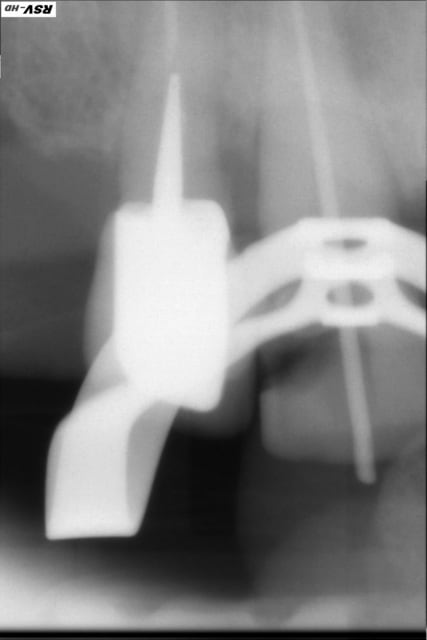

Petite endo bizarre...

très propre